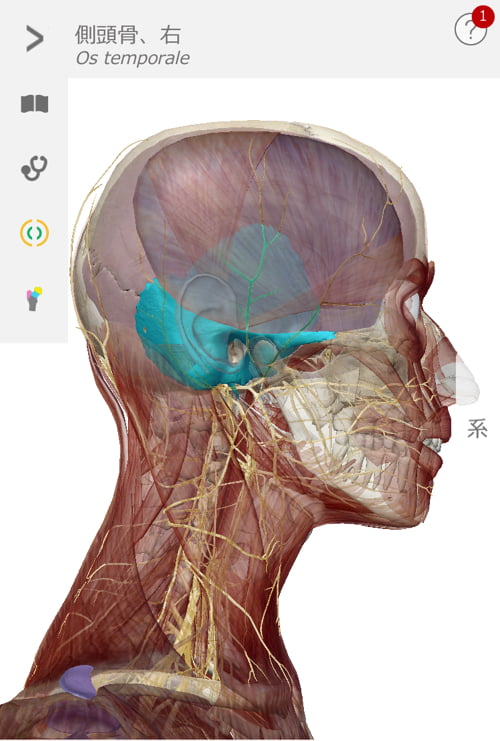

目が疲れて来るとコメカミから側頭部付近が固くなってきます。

まず側頭骨が自由になるように顔周りから耳周りの筋肉を緩めて調え

最後に視神経のルートを辿りながら筋肉や頭骨の微調整をして終了です。